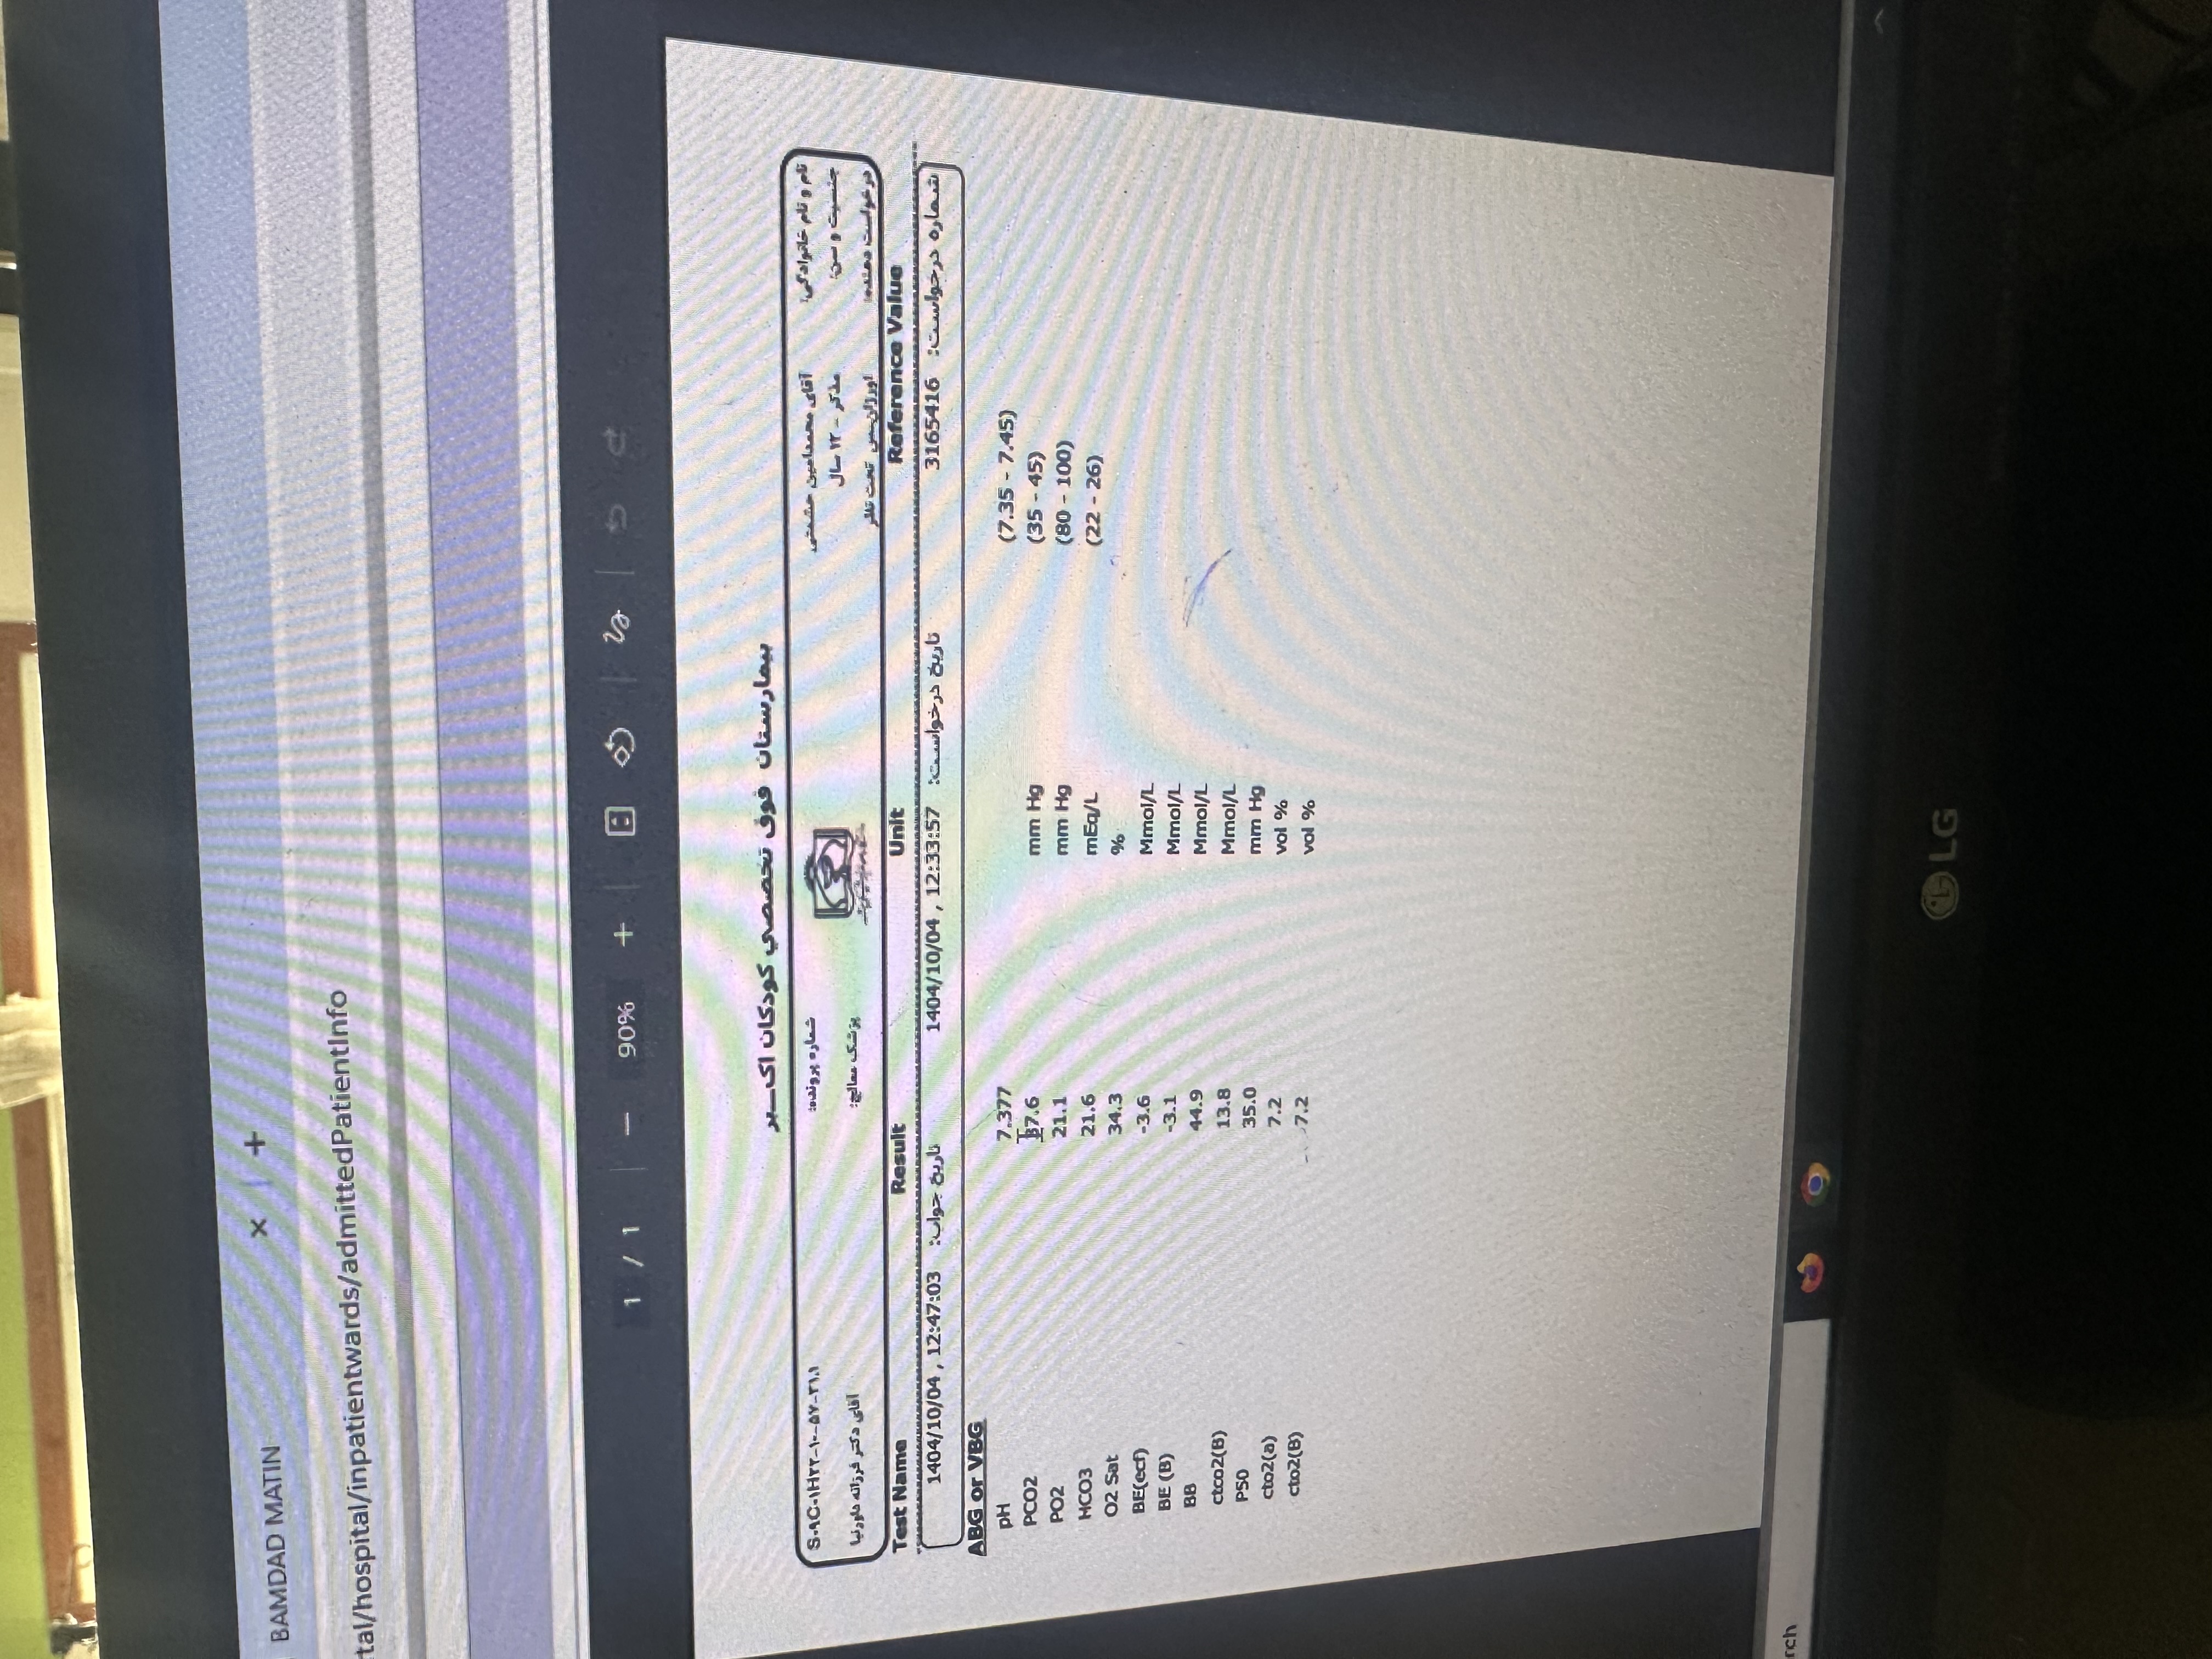

افزایش پترن واسکولار داره با ارجحیت سمت راست ولی دو طرفه، که سمت راست تقریبا به سمت کانسالیدیشن داره پیش میره. چست هم PA هست

عدم نمای پر هوایی=Rule out bronchiolitis